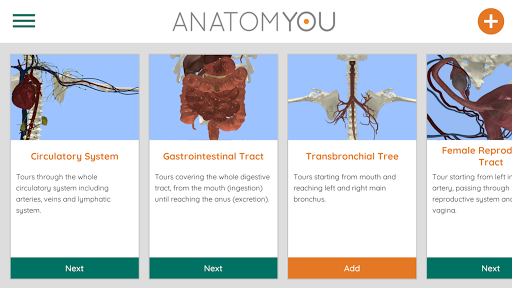

Korzystając z wirtualnej rzeczywistości, będziesz w stanie poruszać się wzdłuż struktur anatomicznych, stając się częścią ludzkiej anatomii: układu rozrodczego układu krążenia, oddechowego, trawiennego, moczowego, łzowego i żeńskiego.

Oferuje bezpłatny dostęp do niektórych tras nawigacji w prawie każdym z wymienionych systemów. Dodatkowa treść do kupienia jest oferowana w sekcji aplikacji w aplikacji.

To nowo odnowiona wersja Anatomyou VR. Dodatki zawarte: - Bardziej realistyczna anatomia człowieka, ulepszająca modele i tekstury. - Lepsza interakcja użytkownika w VR i trybach pełnoekranowych. - Całkowicie odnowione menu i obrazy zapewniają intuicyjną nawigację. - Dodatkowa treść kliniczna potwierdzona przez naszych ekspertów. - Poprzedni użytkownicy muszą zaakceptować pewne uprawnienia (pakiet SDK GoogleVR). Włożyliśmy wiele wysiłku w to ulepszenie, mam nadzieję, że Ci się spodoba!